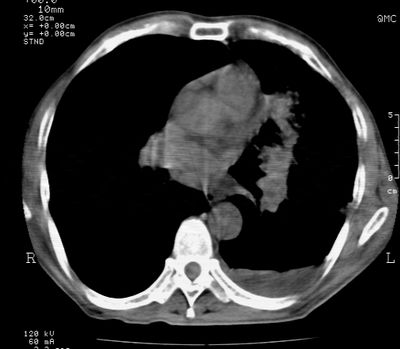

标题: CT24000:M65,胸痛,胸闷月余,既往慢支,肺气肿,肺心病 [打印本页]

标题: CT24000:M65,胸痛,胸闷月余,既往慢支,肺气肿,肺心病

左肺门肿块,相应支气管闭塞,左肺上叶、舌叶大片及散在高密度影,部分呈不张改变,两肺纹粗乱,左侧胸腔积液。考虑左侧中央型肺癌伴阻塞性改变。

左肺门见巨大软组织肿块影,直径约--,境界清,左上肺叶支气管变窄,左上肺舌叶见大片状密实影,余肺纹理增多、紊乱、纤细、部分网格状,两肺透亮度增高,纵隔内见增大多发淋巴结影,心影略左偏,左侧少量胸腔积液。

左侧中央型肺癌伴左上肺舌叶不张、纵隔淋巴结转移,左侧少量胸腔积液。